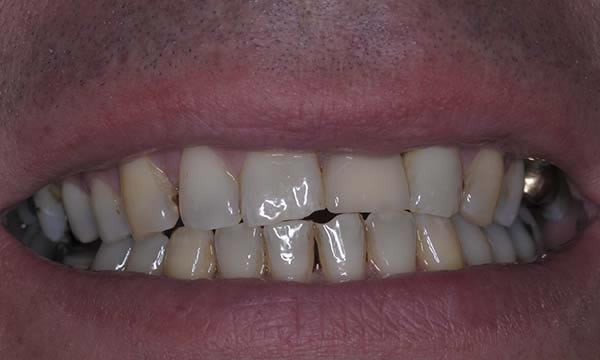

A case of a patient who was a long term resin retained bridge wearer. The resin retained bridge was placed after the patient lost his UL1 many years ago. There was a history of the resin retained bridge lute failing, and due to the loss of the UL1 there was a labio - palatal bone deficit.

A clear acrylic position guide was used to guide implant placement within the aesthetic envelope and guided bone regeneration was used labially to elevate the long standing concavity. A Bonded crown was used to restore the implant and at the 12 month follow up, the bone level around the implant remains unchanged and the patient is confidently smiling.